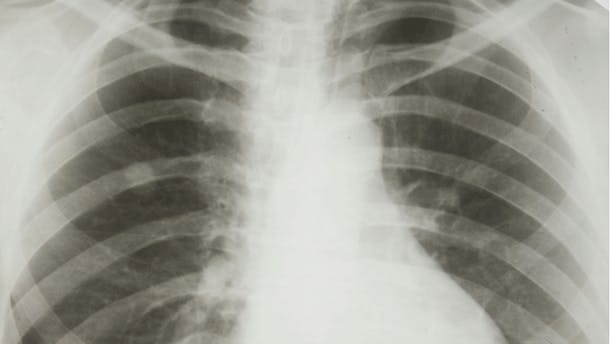

Overlev lungekræft … i Hovedstaden!

Det er langt fra ligegyldigt, hvor du bor henne, hvis du bliver ramt af alvorlig sygdom. I hvert fald ikke, hvis det er lungekræft, viser en detaljeret analyse af i rapporten 'Behandlingsindsats og relateret overlevelse ved lungecancer 2008 - 2010'. Rapporten gennemgår samtlige tilfælde af lungekræft, der er registreret i Dansk Lunge Cancer Register i perioden. Og der er tale om en stor, fælles arbejdsindsats. Rapporten er nemlig lavet i samarbejde mellem lungekræftlæger fra hele landet og er den mest omfattende og grundige af sin slags. Den gennemgår næsten 12.000 tilfælde af den meget alvorlige sygdom, der kræver hurtig behandling, hvis patienten skal overleve sygdommen. Og der er stor forskel mellem regionerne, skriver www.cancer.dk.

I Syddanmark, Midtjylland og Nordjylland er dødeligheden op til 20 procent højere end i Hovedstaden. Blandt andet fordi, der er forskel på, hvem der får tilbudt den mest effektive mulighed for helbredelse - nemlig operation, ligesom der også er forskel på, hvordan og hvornår de enkelte regioner bruger kemo- og strålebehandlingen, viser rapporten. Hovedstadens gode resultater skal selvfølgelig komme alle landets lungekræftpatienter til gode, og derfor skal sygehusledere i resten af landet sørge for at organisere deres indsats, så de når samme høje niveau, siger kræftens Bekæmpelses direktør, Leif Vestergaard Pedersen.